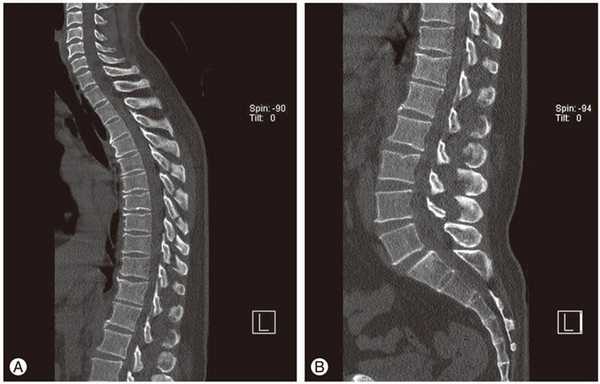

- МРТ или КТ. Проведение исследований позволяет обнаружить изменения межпозвонковых дисков, оценить состояние связок, мышц, кровеносных сосудов, спинномозговых корешков.

- КТ

В сети клиник ЦМРТ при диагностике различных дорсопатий, магнитно-резонансная томография выполняется в комплексе с мануальным тестированием. Совокупное применение данных методик дает полную информацию о локализации участков дискогенных нарушений, о структуре и метаболической активности клеток, состоянии всех мягкотканных компонентов.